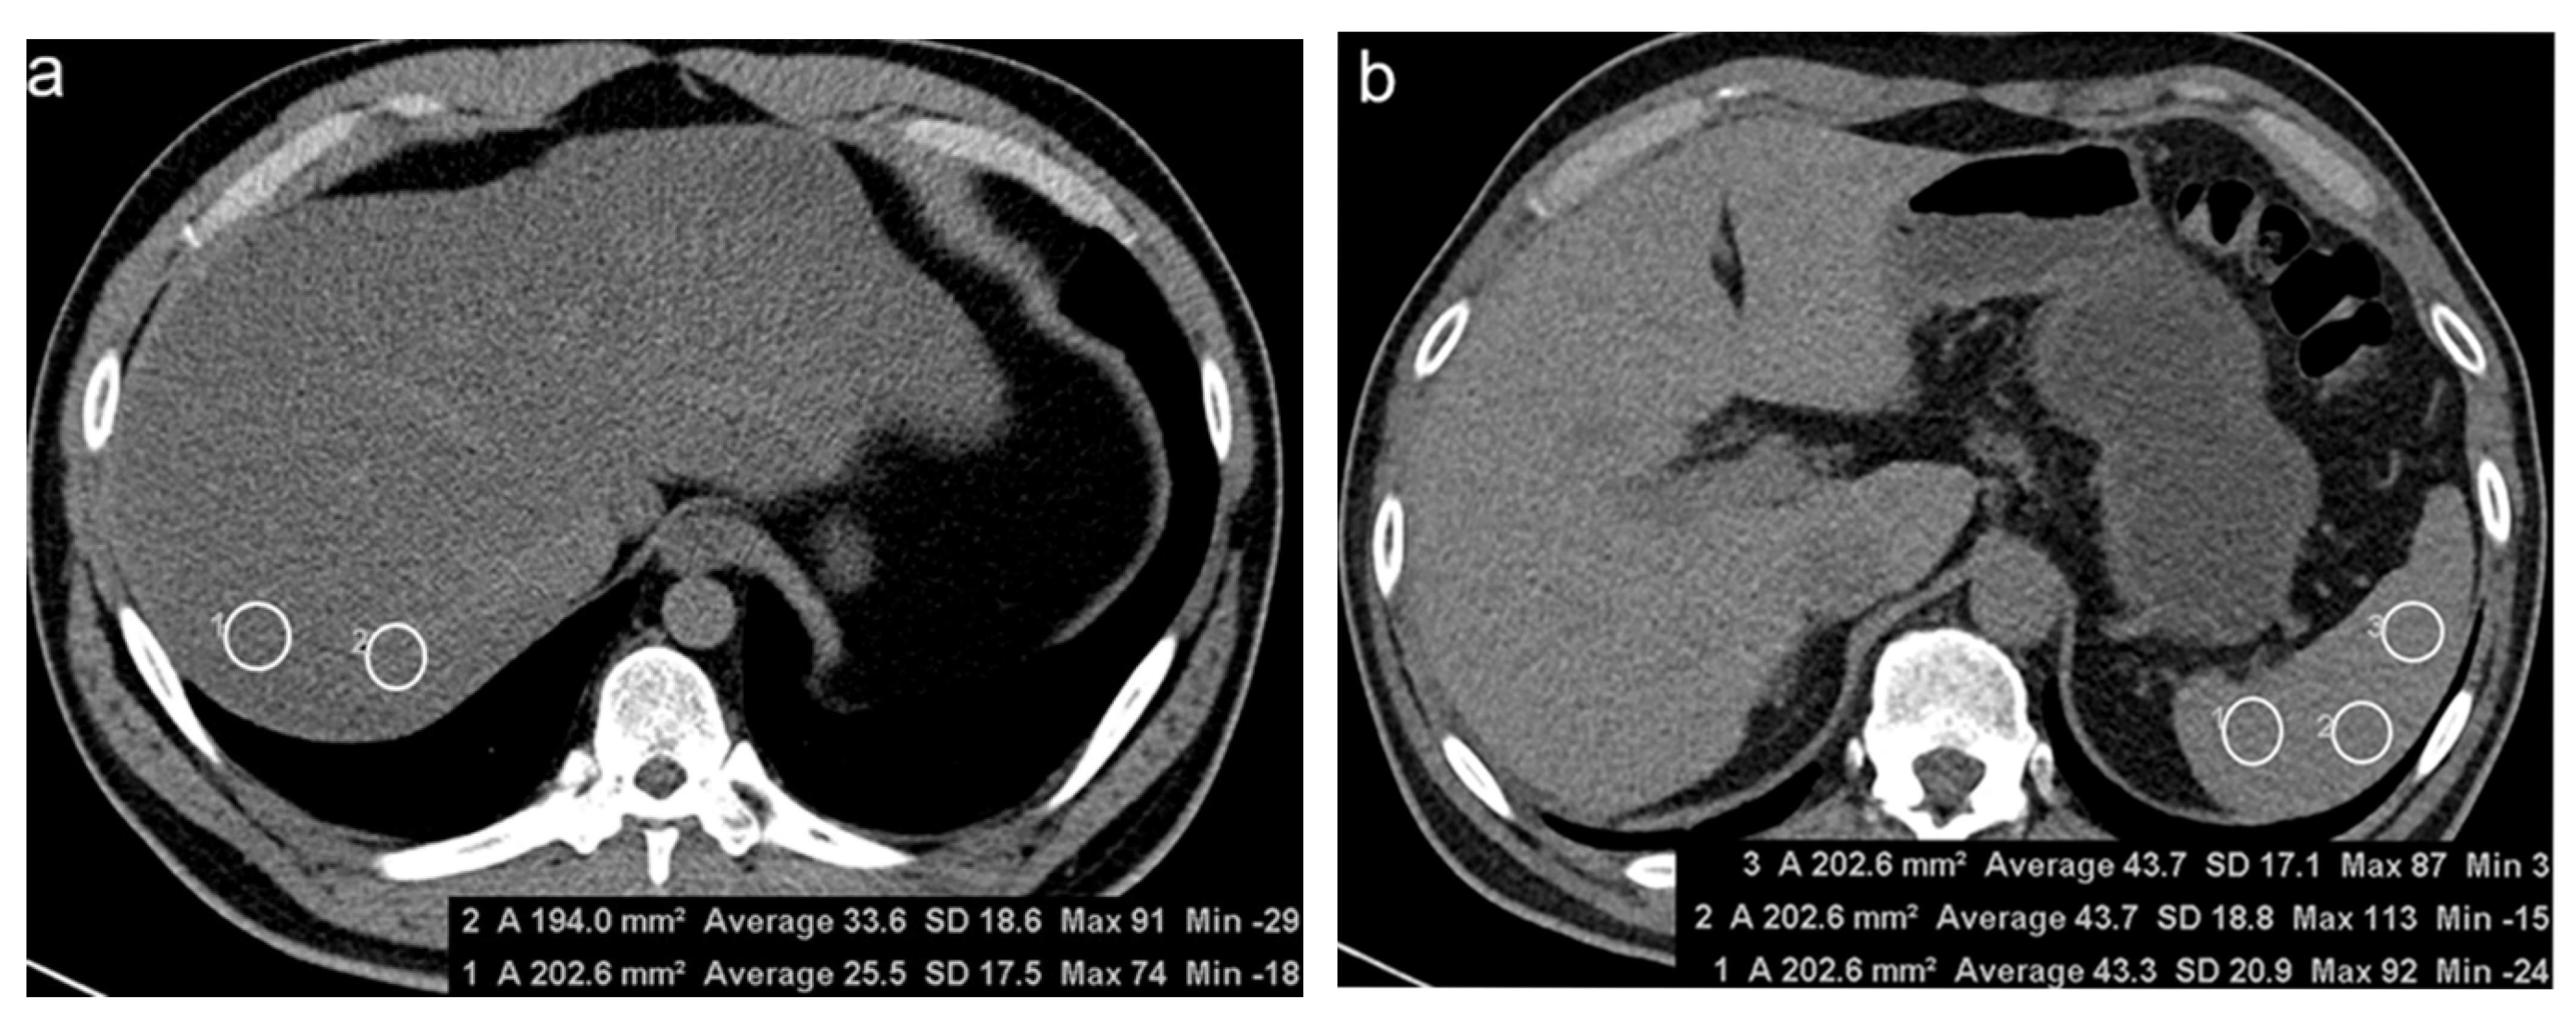

2.2. CT Examinations

2.3. Image Analysis